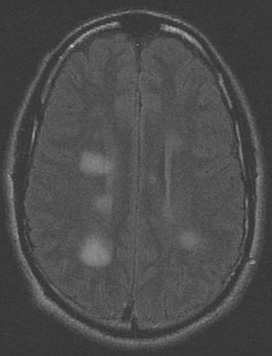

Séries de imagens de ressonância nuclear magnética (RNM) do cérebro de um paciente com encefalomielite disseminada aguda: lesões assimétricas "felpudas" sobre os cornos ventriculares bilaterais e tálamos

Do acervo pessoal de Catalina C. Ionita, MD; usado com permissão